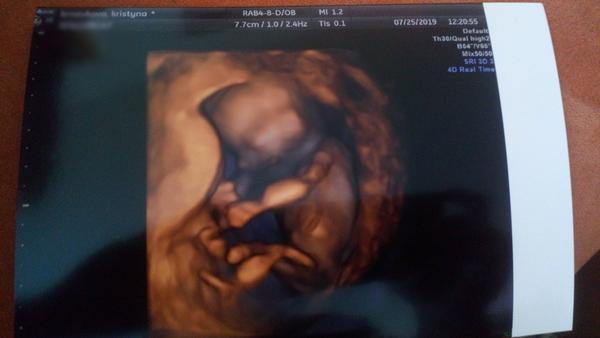

@anna189 mě doktorka na screeningu říkala když to zkoumala tak že je tam jako kdyby takový ovalek hodně dovrchu a pupečník to nebyl a že u holčičky to není tak viditelný že je to spíš jako tvar meruňky ty stydky pysky. A že mi to pohlaví potvrdí na 100% na druhém screeningu na který jedu 11.9